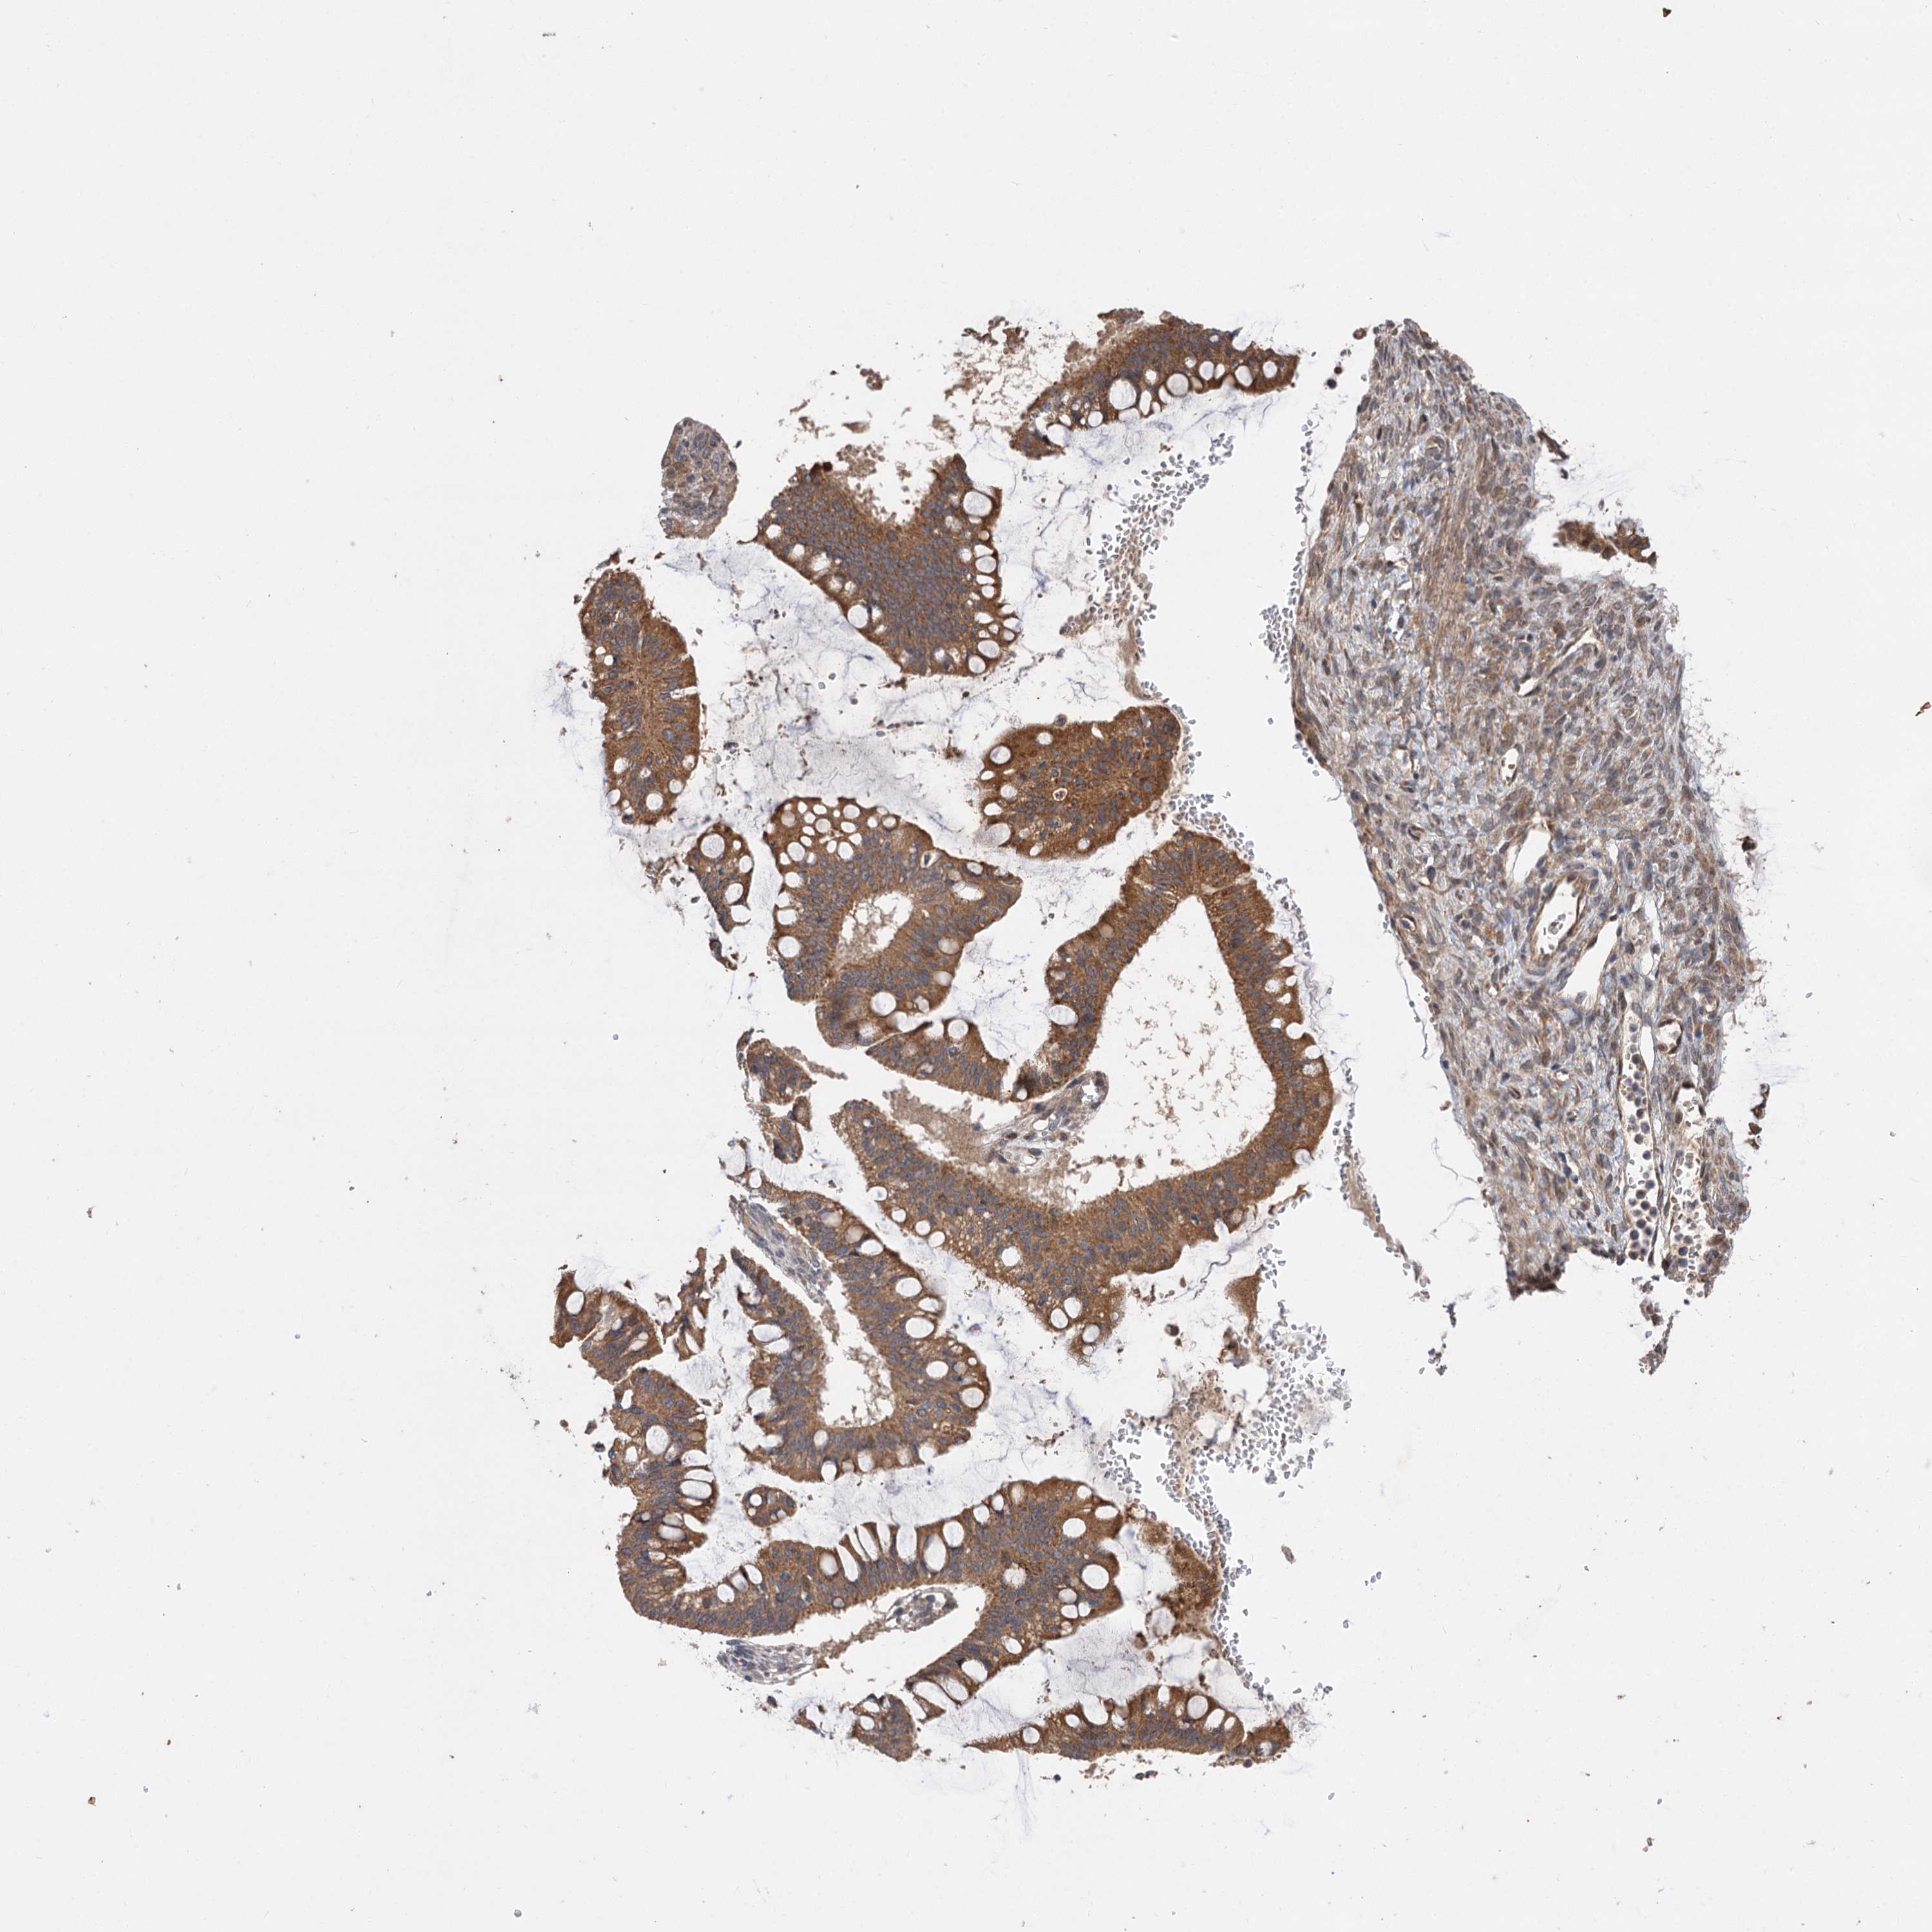

OVARIAN CANCER - Protein expressioni

A mouse-over function shows sample information and annotation data. Click on an image to view it in a full screen mode. Samples can be filtered based on level of antibody staining by selecting one or several of the following categories: high, medium, low and not detected. The assay and annotation is described here.

Note that samples used for immunohistochemistry by the Human Protein Atlas do not correspond to samples in the TCGA dataset.

Antibody stainingi

Antibody staining in the annotated cell types in the current human tissue is reported as not detected, low, medium, or high, based on conventional immunohistochemistry profiling in selected tissues. This score is based on the combination of the staining intensity and fraction of stained cells.

Each image is clickable and will lead to virtual microscopy that enables deeper exploration of all samples and also displays staining intensity scores, fraction scores and subcellular localization as well as patient and tissue information for each sample.

Antibody HPA038850

Antibody HPA038851

Cystadenocarcinoma, serous, NOS

Carcinoma, endometroid

Cystadenocarcinoma, mucinous, NOS

Carcinoma, NOS